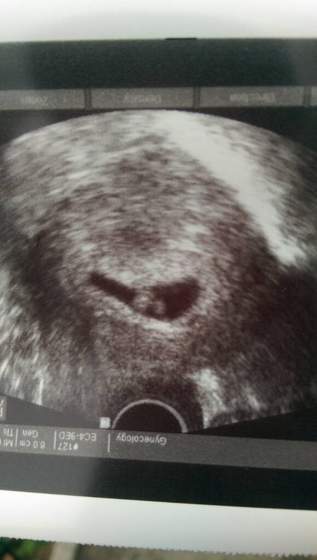

Zrobiło mi się przykro, wytłumaczyłam, chyba coś zrozumiał... Tylko w sumie nie mam do niego pretensji, w końcu to nasza pierwsza ciąża i każde z nas jest trochę jak dziecko we mgle, ale same wiecie ile to nerwów... Oby z czasem było lepiej.